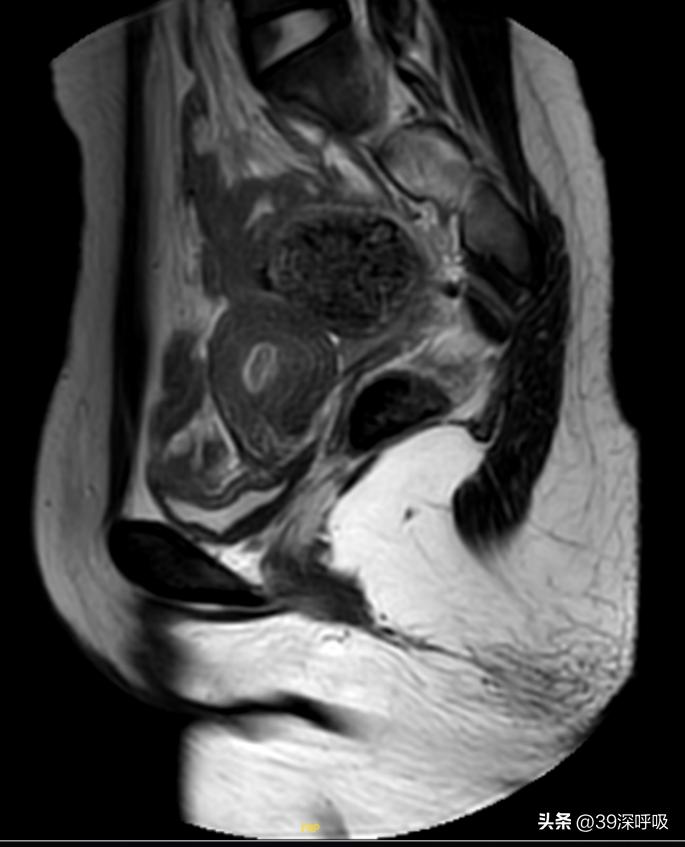

“确实是无阴道,孩子之所以出现周期性的下腹疼痛,正是因为有月经血,但没有通道排出所致,你们马上办理住院做进一步详细检查。“谢梅青作出专业的判断,为小黄揭开了谜团。 小黄住院后的盆腔MRI检测,诊断为先天性阴道闭锁II型:即阴道完全闭锁、宫颈闭锁。

◎ 妇科超声及盆腔MRI检查提示小黄患有II型阴道闭锁。/ 医生供图